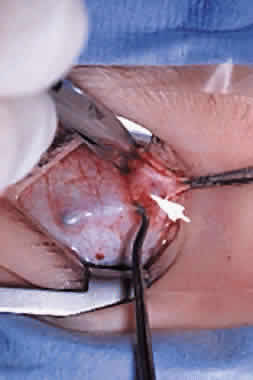

The superior oblique tendon tuck is best performed near the tendon's insertion as described by McLean.48 The surgical procedure is performed through a superior temporal cul-de-sac approach (Fig. 4). With the globe depressed, an incision is made through the conjunctiva and Tenon's fascia just temporal to the lateral border of the superior rectus muscle and parallel to the corneoscleral limbus. The superior rectus muscle is engaged on a muscle hook and the globe adducted and positioned in maximal depression. The lateral rectus muscle may also be used to assist positioning the globe. Using two small muscle hooks, the conjunctival incision is stretched open posteriorly in a triangular fashion. The lateral border of the superior rectus muscle is elevated and displaced medially. The globe is then examined for the glistening, white fibers of the superior oblique tendon running flush against the sclera and directed anteromedially. The anterior portion of the reflected tendon typically inserts under the lateral border of the superior rectus muscle, 5 to 7 mm posterior to its insertion. However, this location may vary, and anatomic anomalies are common (Fig. 5).12,37,47,48 The superior oblique tendon looks very different near its scleral insertion than 10 mm more proximally, where it becomes cordlike and enters Tenon's fascia after passing under the belly of the superior rectus muscle. Inexperienced surgeons have mistaken the lateral portion of the tendinous insertion of the superior rectus muscle for the superior oblique tendon (Fig. 6).49 However, the superior rectus muscle travels toward the orbital apex and contains prominent anterior ciliary blood vessels, whereas the superior oblique tendon is directed toward the trochlea and is usually avascular. In addition, direct traction on the superior oblique tendon can easily be palpated at the trochlea by pressing a finger over the eyelid in the superior nasal quadrant of the orbit.10 This is a reliable sign that the tendon (and not some other structure) has been engaged on the muscle hook.

After the superior oblique tendon has been positively identified, it is gathered on a Stevens tenotomy or other muscle hook with a small tip. This maneuver is most readily accomplished by passing the hook over the tendon with its tip parallel to the sclera and pointed medially. Direct visualization of the tendon is essential, in that blind sweeping can be hazardous. A superior temporal vortex vein usually exists near the posterior insertion of the superior oblique tendon and the optic nerve is within reach. In addition, it is important to avoid passing the muscle hook into orbital fat because its release into the sub-Tenon's space predisposes the eye to develop an adherence syndrome postoperatively.50